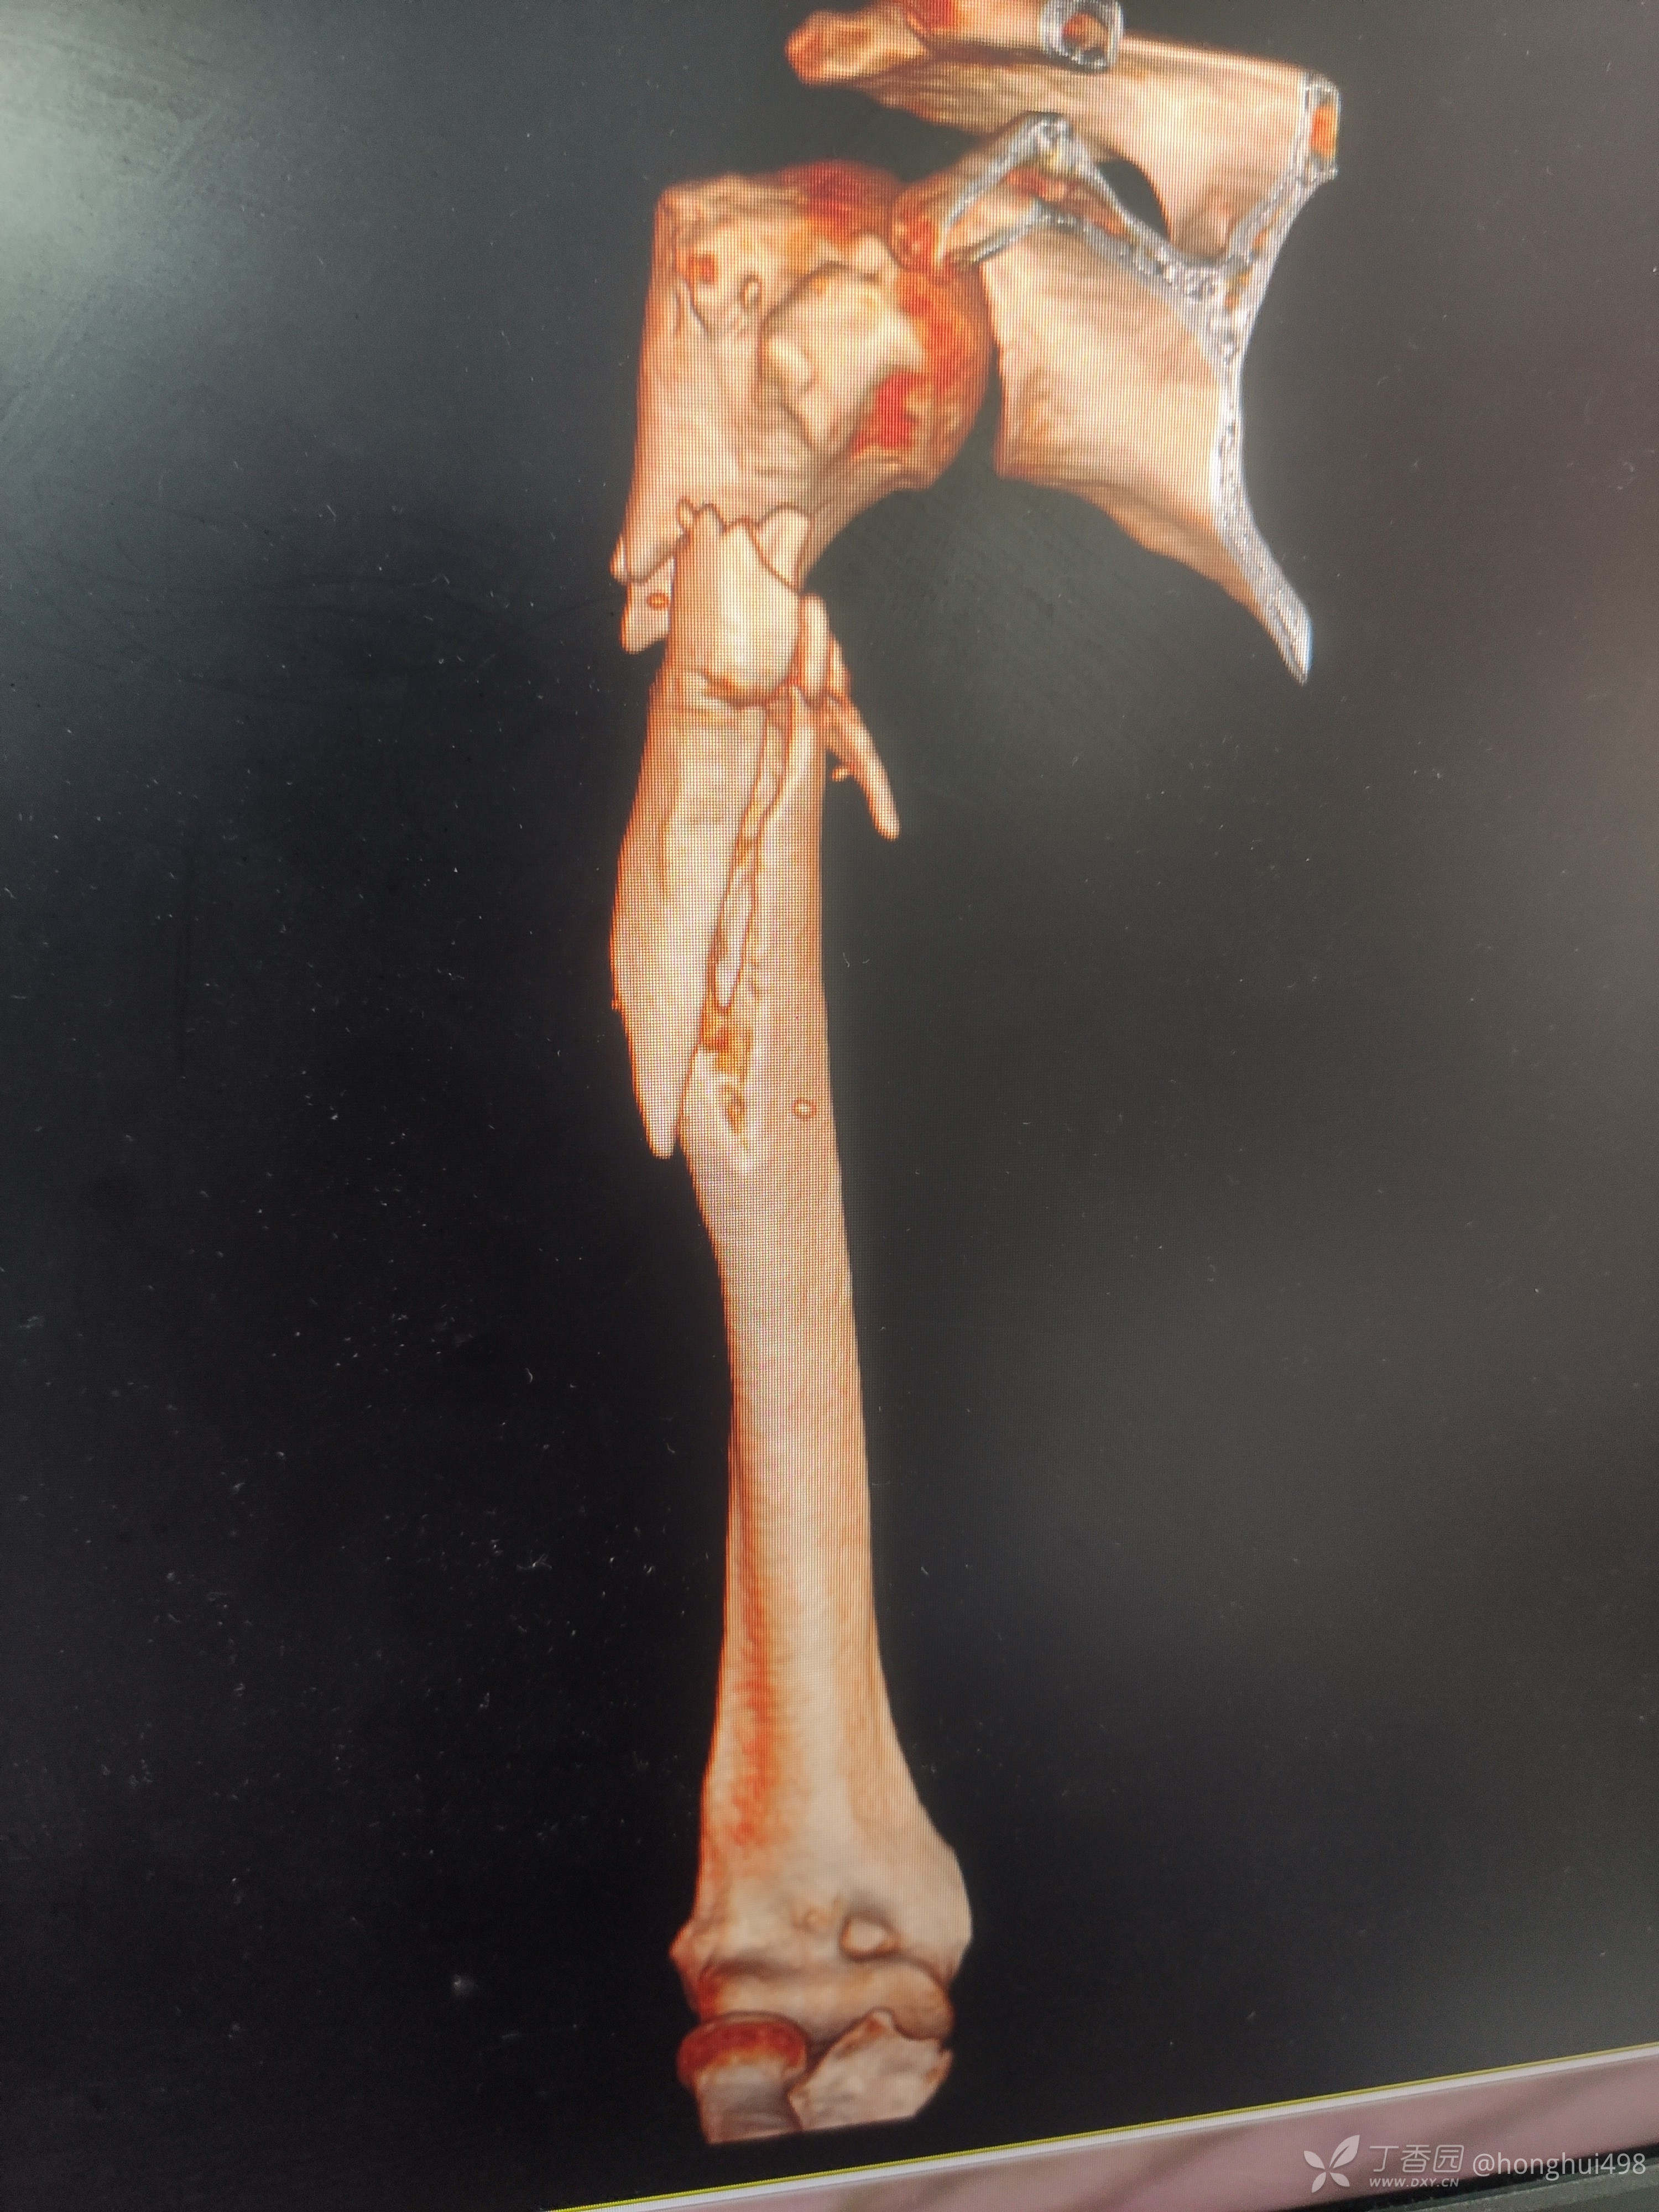

男性患者,62岁,摔倒致伤,入院诊断右肱骨骨折。麻醉下行肱骨骨折有限切开复位髓内钉+钢缆固定。

肱骨髓内固定做得比较少,但是手术还是顺利,此例患者你们如何选择固定方式?欢迎讨论